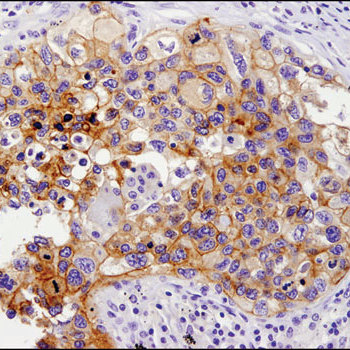

使用PD-L1 (E1L3N®) XP® Rabbit mAb #13684

对石蜡包埋的人肺癌样品进行免疫组织化学染色。

中山大学肿瘤防治中心使用PD-L1(E1L3N® )XP®

Rabbit mAb #13684染色石蜡包埋的肝癌组织切片。